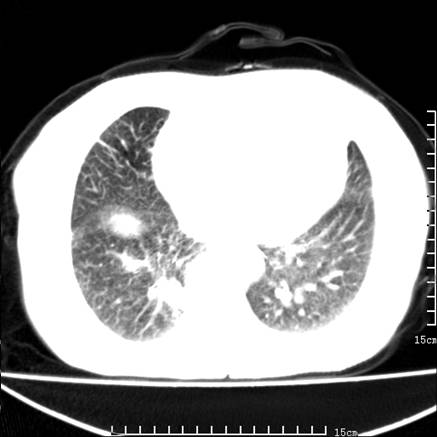

女,王某,58岁,咳嗽三个月余,基层医院二个月前诊为肺结核,用抗结核药二个月无明显疗效。

心包积液致肺瘀血.右侧周围型肺癌伴肺内转移,中间裂积液,叶间胸膜肥厚.右上肺大泡,右侧胸膜肥厚.

双肺继发型tb,心功能不全并肺淤血、心包、双侧叶间裂积液,肺大泡,右下胸膜肥厚钙化。